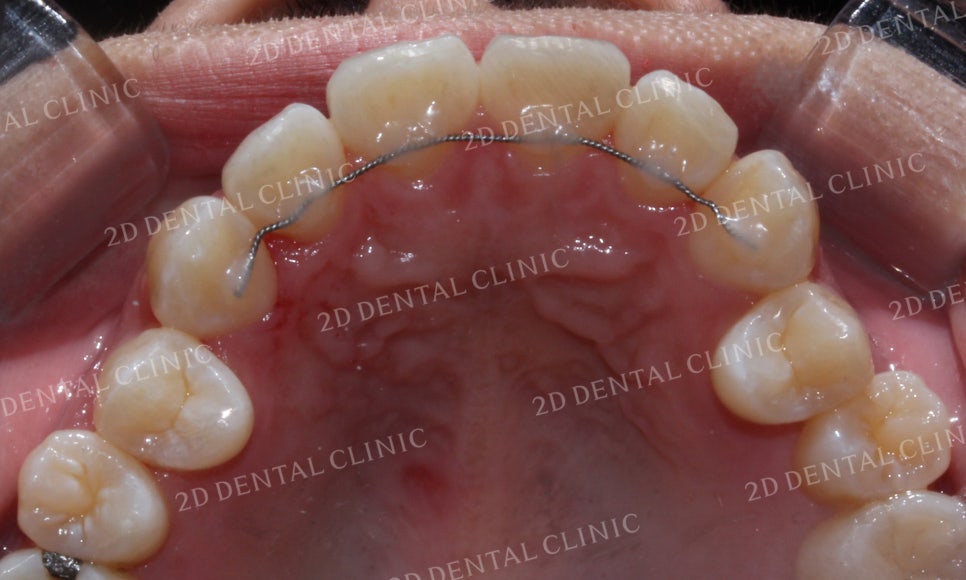

상악의 설측면 사진입니다.

교정 전 전치부의 치아배열을 보시면

크라우딩이 심해서 앞니가 대각선으로

틀어진 모습이 보입니다.

교정 후 치아 사진에서는 6개의 치아 모두

제자리를 찾아 배열된 모습이네요.

이번 Case의 환자분은

크라우딩이 심한 전치부의

치아만을 교정하시기 원하셨습니다.

따라서 구치부의 치아들은

교정을 진행하지 않았습니다.